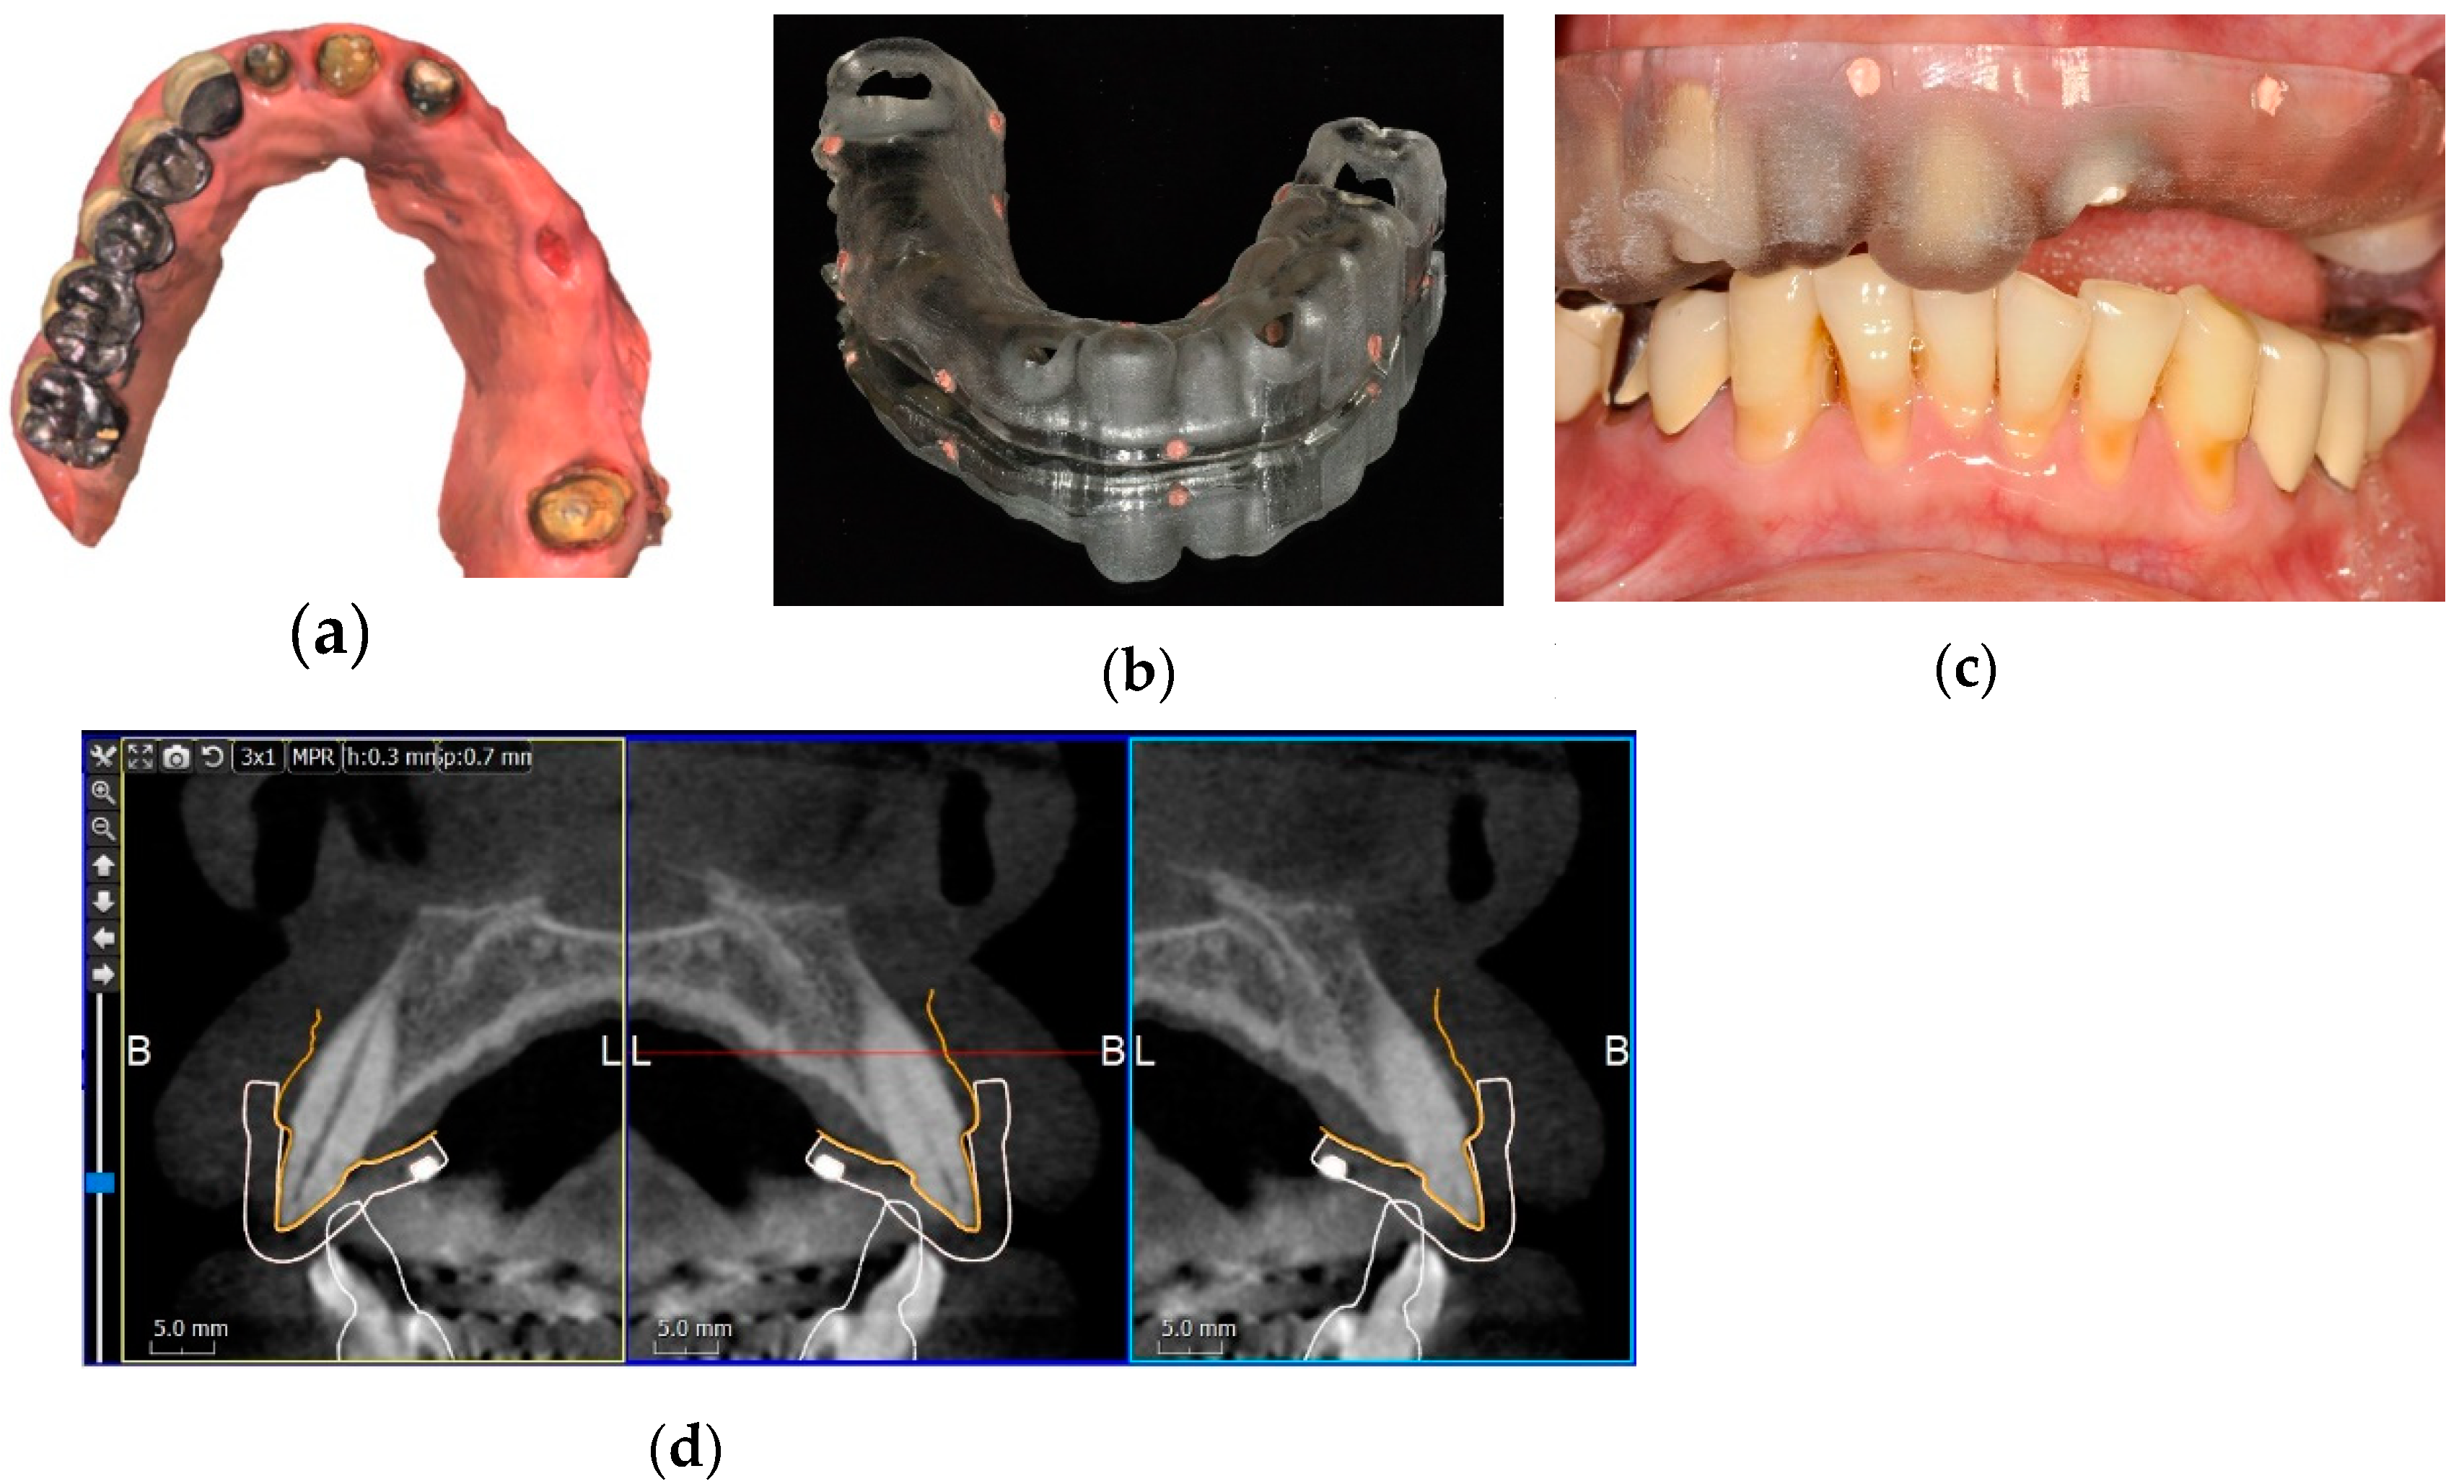

Figure 2.

Fiducial marker protocol of implant planning. (a) An occlusal image of a maxillary intraoral scan. Five metal crowns on the right side and the inadequate number of residual teeth made the correct alignment of CBCT and intraoral scans by dental surface registration difficult. (b) Using the digital data of the intraoral scan, a stereolithographic (SLA) radiographic template with gutta-percha fiducial markers was fabricated. (c) The SLA radiographic template in the mouth ready for a CBCT scan. (d) A CBCT image aligned with the intraoral scan image (orange line) by matching the fiducial markers (white cubes) on the SLA radiographic template (white line).